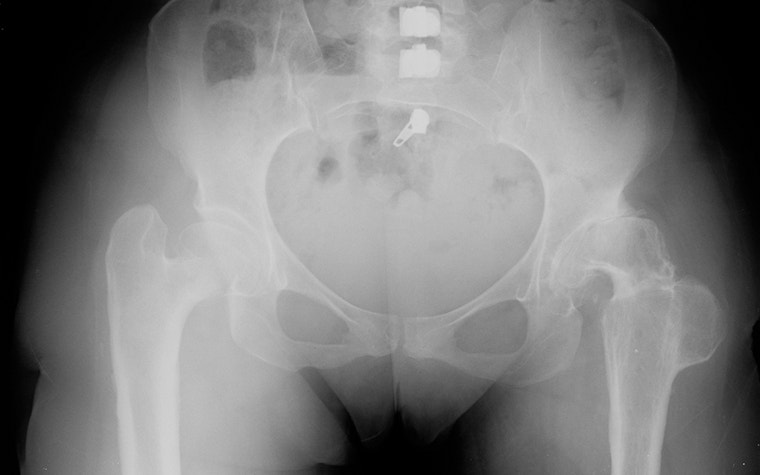

The patient was a female in her late 40s with a long history of DDH. Based on the preoperative X-ray below, it’s evident that she has had previous surgery on her right hip. However, on the left hip, the need for a total hip replacement was identified due to intractable pain.